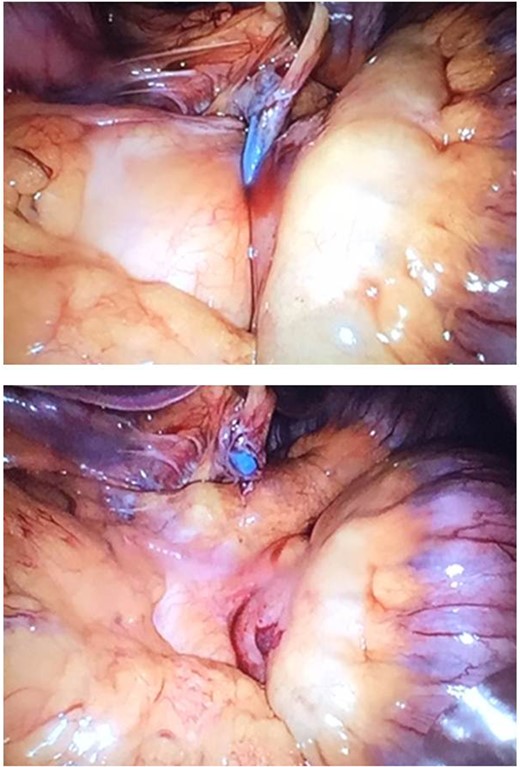

Diagnostic laparoscopy showed an ileus. Inspection along the alimentary limb resulted in locating the minimizer ring at the transition of alimentary limb and common channel. After removal of this ring, the biliopancreatic limb and common channel were visible again (Fig. 2). From the common channel, there were non-dilated intestinal limbs. The problem seemed resolved. There were no adverse outcomes for both the mother and the fetus.

Upper picture: minimizer ring around the jejunojejunostomy. Lower picture: removal of the minimizer ring.